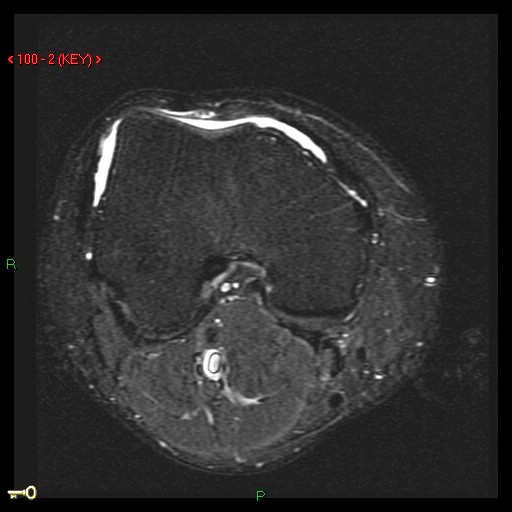

27 y/o patellar tendon rupture with repair 2 years ago. Re-injury 1 year ago. Now with increasing pain and limited range of motion.

Figure 3 for case Patellar tendon re-tear

Figure 3

The acute changes have resolved but the patient has a re-tear of the tendon. The patella is retracted superiorly. Important to measure the length of gap as well as any residual tendon for surgical planning.

Patellar tendon re-tear